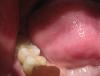

MamAnuta Опубликовано 31 октября, 2013 Поделиться Опубликовано 31 октября, 2013 Доброго времени суток, уважаемые специалисты!Заранее извиняюсь, за качество снимков - домашняя фотосессия завтра попробую запросить их по электронке с клиники. Сама проживаю в другом городе. Год назад мне установили имплантанты на нижней челюсти 2 шт на место 6 и 7 зуба справа (винтовые Ankylos)Коронки поставили только 29 окт (т.к. верхние зубы "провисли" и было принято решение их "повернуть" к центру и "поднять" чтобы не спиливать при установке коронок - это заняло 6 мес).При выборе материала коронок мне предложили либо металлокерамику либо циркониевые. Я выбрала цирконий, т.к. сказали, что получше... эстетичнее что ли... Если честно, я думала, что циркониевые зубы, да и вообще имплантантированные зубы, выглядят как настоящие, только без дефектов... У меня же получился вид своего собственного, но только леченого перелеченого (как будто был кариес во всю полость зуба и закрыт более светлой пломбой), а посередине кругленькие желтенькие пломбочки, закрывающие технологические отверстия.Вид никакой об эстетике вообще молчу - ее там нет... При установке коронок (их сделали две слитные, но в каждой коронке отдельное отверстие для фиксации) я сразу высказала сомнение в цвете жевательной поверхности, т.к. она сильно (на мой взгляд) отличалась от других своих зубов и от боковой поверхности самих коронок.На что врач сказал, что это такие технические нюансы - так изготавливается коронка. Но после консультации в соседнем кабинете с кем-то по телефону сказал, что можно сделать и по-другому, но надо будет доплатить по 12тыс за каждую коронку за изготовление абатментов - вроде так их называл (я не специалист, поэтому могу врать в терминах).И вообще я первый в его практике пациент, который предъявляет претензии к цвету жевательной поверхности зуба - мол все равно ее никому не видно...Я сказала, что раз по-другому сделать технически нельзя, то пусть ставит так как есть.Подгоняли очень долго - все что-то мешало при накусывании. Долго отпиливали то ли сверху зубы, которые полгода выпрямляли, чтобы не пришлось стачивать, то ли снизу зуб за 50 тыс - даже не поняла Вроде все подпили, все хорошо, отфотографировали... дали зеркало...На вопрос почему нельзя было подобрать цвет этой пломбы под цвет поверхности зуба, доктор вспылил и сказал, что не понимает, что мне не нравится, а потом вообще сказал чтобы я приходила в другой день и они все переделают, никакой доплаты не нужно, просто все будет менее надежно и практически выгнал меня из кабинета, не объяснив больше ничего (у него был уже следующий человек по записи). В связи с этим вопрос - как должны выглядеть нормальные коронки в моей ситуации?Действительно я слишком придирчива и это НЕВОЗМОЖНО сделать иначе технически? Тогда почему врач сказал что переделают за свой счет? Что они мне там сделают - уже даже и думать не хочется Просмотрела кучу фото в интернете циркониевых коронок и такого чуда как у меня нигде не нашла На самом деле хочется послушать профессионалов - может я зря на доктора обижаюсь? Но тогда странно, что за все это убожество надо платить ТАКИЕ деньги - 2 зуба обошлись более чем в 100тыс руб...Муж считает, что я придираюсь, хотя у самого год назад вставлено тоже 2 зуба в этой же клинике - на них не видно ничего - просто обычные нормальные зубы. Хочется объективности - прошу Вашей помощи Ссылка на комментарий

MamAnuta Опубликовано 2 ноября, 2013 Автор Поделиться Опубликовано 2 ноября, 2013 это винтовая фиксация коронок. В них действительно есть технологическое отверстие - это их минус. Но есть и плюсы.На абатменте можно сделать цементную фиксацию, там нет технологических отверстий, но есть другие минусы. Истина где-то посередине.http://forum.stom.ru/topic/23130-vintovaia-vs-tcementnaia-fiksatciia-koronok-na-implan/Спасибо большое!Все прочитала, что стало понятнее, что-то совсем не поняла (т.к. не врач) Что касаемо моей ситуации... раз уж сделали винтовую, пусть будет винтовая. Мне на самом деле не принципиально - раз врач решил в моем случае сделать винтовое крепление - ему виднее. Меня больше смущает эстетика, внешний вид моих зубов.Но фото винтовых коронок, что я увидела все-таки сильно отличаются от того, что поставили мне. На снимках, вывешенных врачами, они везде одинаковы по окраске со всех сторон, у меня же получился как ободок моего цвета вокруг светлой жевательной поверхности.До подгонки этого ободка не было, была просто светлая жевательная и моего цвета боковая поверхность. После подгонки образовался ободок, видимо из-за того, что подтачивали саму коронку и стал виден этот наружный слой на срезе.А шахты, выходит, просто безобразно (=некрасиво) и неумело запломбировали Подскажите, возможно ли в моем случае сделать приличную циркониевую коронку, чтобы она не отличалась по внешнему виду от остальных зубов без всяких полосок, ободков и пр. (шахты я уверена можно закрыть так, что их не будет видно) ? Ссылка на комментарий

MamAnuta Опубликовано 2 ноября, 2013 Автор Поделиться Опубликовано 2 ноября, 2013 Вам же предложили переделать... СоглашайтесьДа я и не против Просто мне, идя на следующий прием, надо знать на что я могу рассчитывать и что можно сделать технически, а что нельзя.Поскольку в этом совсем не разбираюсь, многих нюансов не знаю, то меня легко ввести в заблуждение, вот и хочется разобраться, чтобы не быть слепым котенком скорее да, чем нет.то есть то, что сказал мне доктор, что технологически сделать жевательную поверхность одного цвета с боковой невозможно - это неправда? И еще смущает несколько форма зубов - она не слишком ли бочкообразная?? И вообще, уважаемые профессионалы своего дела, не могли бы вы прокомментировать фото коронок, которые мне изготовили, как вы обсуждаете работы друг друга в соответствующей теме. Я просмотрела их - многие просто великолепны и нисколько не отличимы от нормальных зубов - я в большинстве случаев и угадать не могу где и что, а вот то НЕЧТО, что находится сейчас у меня во рту, я даже не знаю как и назвать... порнография какая-то... (прошу прощения за мой французский ) Ссылка на комментарий